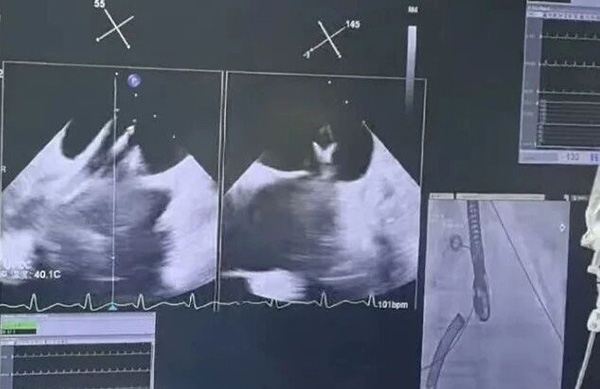

“反流显著减少了!”在北京地坛医院导管室内,随着经食道超声屏幕上数据的跃动,心内科、麻醉科、导管室团队医护人员紧绷的脸上终于露出了欣慰的笑容,这已经是本月第三例高难度TEER手术。

近日,医院心内科、麻醉科、导管室专家团队完成三例高难度经导管二尖瓣缘对缘修复术(TEER),为三位病情复杂、外科手术风险较大的重度二尖瓣反流患者带来了“心”生。

心脏二尖瓣,如同左心房与左心室之间的“单向阀门”,一旦出现重度反流,就好比“阀门”没关严,导致血液倒流,极易引发心力衰竭。传统开胸手术需要锯开胸骨、让心脏停跳,手术风险极大,这就将高龄、合并症多或心功能差的患者拒之门外。TEER技术,就像派出一支“微创部队”,通过大腿根部血管的微小穿刺,将一枚精巧的“夹子”送至心脏病变部位,精准夹合关闭不全的瓣叶,从而显著减少反流。无需开胸和心脏停跳,就能完成对“生命阀门”的精准修复。

第三位患者李先生(化名)则被诊断为Barlow综合征,这种复杂的瓣膜病变意味着他心脏的“阀门”不仅关不拢,而且组织还特别脆弱,对修复的精准度和稳定性要求极高。专家们在实时超声的“导航”下,用2枚夹合器牢固地锁定了脱垂的瓣叶,术后反流基本消失。